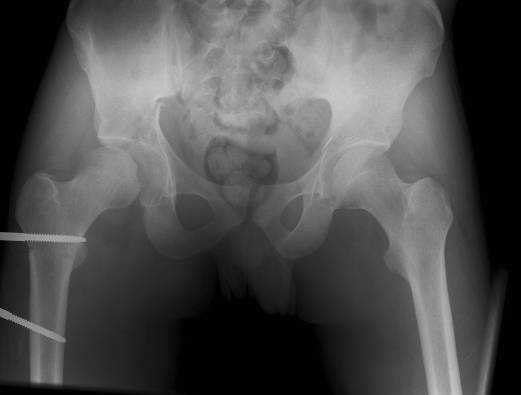

The details of the fracture are not so clear from the images sent...would you be able to send along an AP and Judet images as well as some additional axial images above and below the joint?

Without complete CT images and/or oblique radiographs, it's difficult to answer your question definitively, but it appears that there may not be a posterior wall fracture that requires a posterior approach. A successful reduction through an ilio-inguinal approach will have a faster recovery, and not risk SGN injury or heterotopic ossification.

Here are some more axial images. What is your opinion as for the timing of the operative treatment?

posterior approach, ORIF